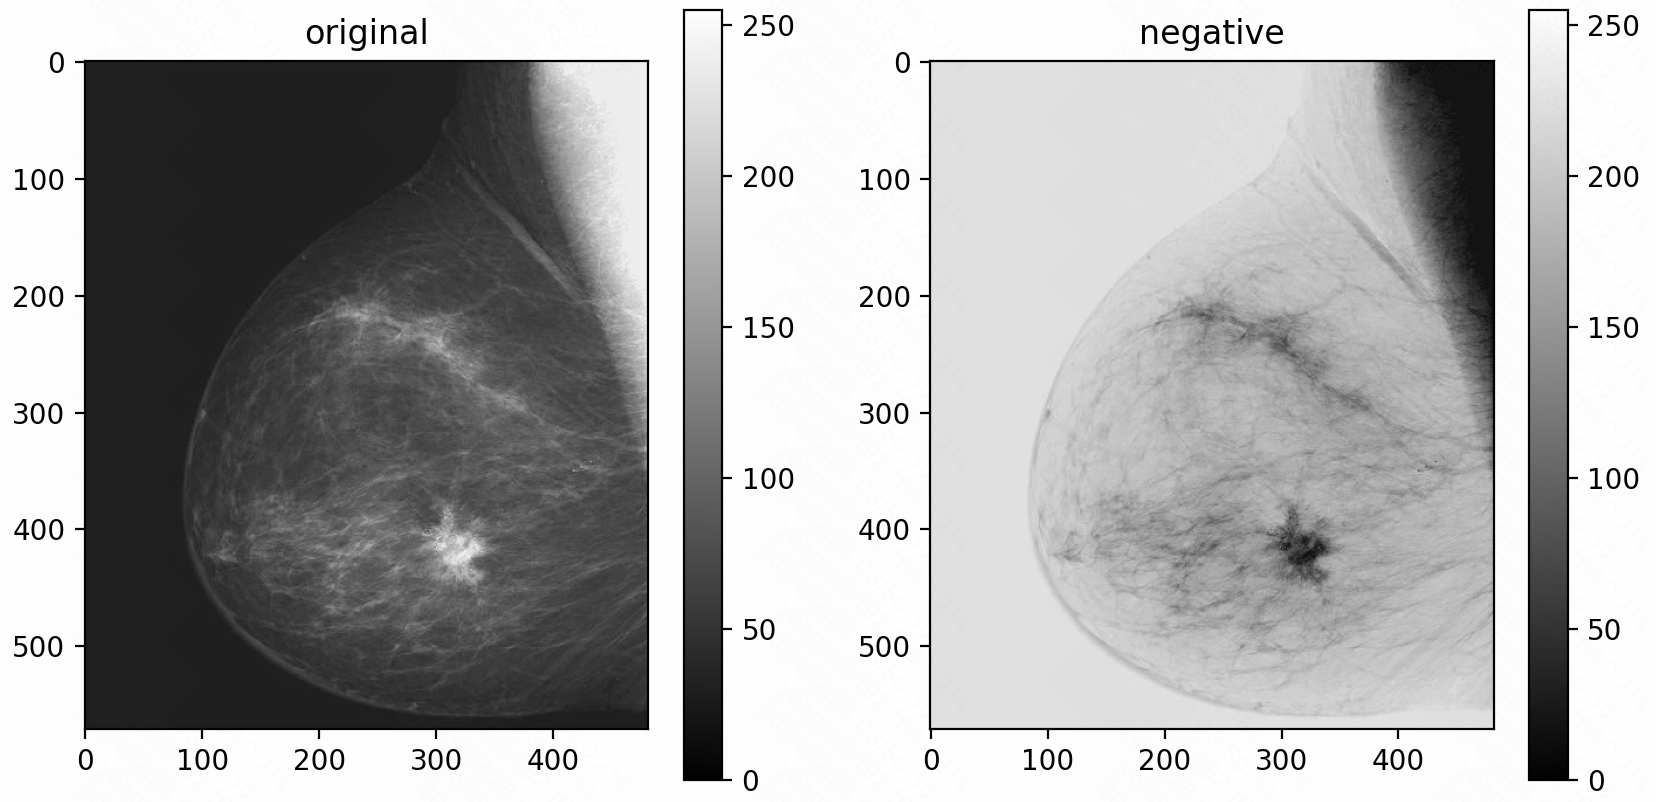

Image Negative: Inverts the pixel intensities, transforming bright areas into dark and vice versa. This is particularly useful in applications like medical imaging.

util.invert(img) # image negative